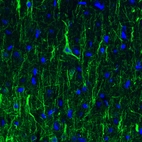

Immunohistochemical staining of human cerebellum shows strong cytoplasmic immunoreactivity in cell bodies and proximal dendrites of Purkinje cells.